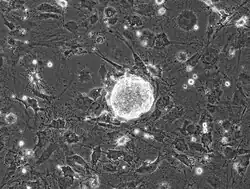

Induced pluripotent stem cells, commonly abbreviated as iPS cells or iPSCs, are a type of pluripotent stem cell artificially derived from a non-pluripotent cell, typically an adult somatic cell, by inducing a "forced" expression of certain genes and transcription factors.[16] These transcription factors play a key role in determining the state of these cells and also highlights the fact that these somatic cells do preserve the same genetic information as early embryonic cells.[17] The ability to induce cells into a pluripotent state was initially pioneered in 2006 using mouse fibroblasts and four transcription factors, Oct4, Sox2, Klf4 and c-Myc;[18] this technique, called reprogramming, later earned Shinya Yamanaka and John Gurdon the Nobel Prize in Physiology or Medicine.[19] This was then followed in 2007 by the successful induction of human iPSCs derived from human dermal fibroblasts using methods similar to those used for the induction of mouse cells.[20] These induced cells exhibit similar traits to those of embryonic stem cells (ESCs) but do not require the use of embryos. Some of the similarities between ESCs and iPSCs include pluripotency, morphology, self-renewal ability, a trait that implies that they can divide and replicate indefinitely, and gene expression.[21]